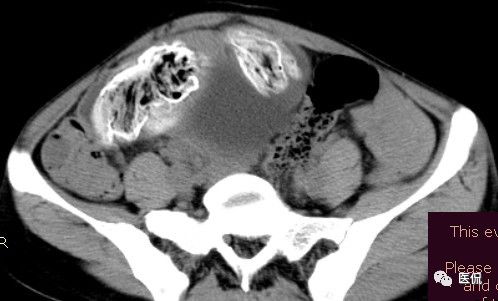

腹腔内残留的纱布在人体内引起渗出或液化坏死并纤维包裹形成异物性脓肿(纱布瘤)。纱布瘤的影像特点:圆形或卵圆形肿块,较大,有完整包膜,薄壁,较少的情况下为厚壁,边界较完整,增强后薄膜可以持续强化。不同时期的纱布瘤可以有不同表现:早期(10个月或半年内)多表现为蜂窝状;2~5年内一般表现为囊性飘带状;10~20年之后则为实性软组织密度,包膜钙化呈钙化网状结构。手术过程中残留在人体内的医用纱布所形成的肿瘤样病变。

手术所见:腹腔内无腹水,肿块位于右上腹,约15x10x8cm大小 ,周围网膜包裹粘连,向胆囊三角处延续,呈囊性,与周围结构无明显浸润,仔细分离粘连,逐步游离暴露肿块,见肿块与右肾及结肠、十二指肠无明显关系,初步确定为肿大的胆囊,继续向肝门部游离,见肿块与胃窦粘连,因分离困难,决定切开肿块。穿刺肿块有黄色脓液抽出,考虑胆囊脓肿,切开囊壁,吸出大量黄色混浊脓液约1200ml,探查囊腔,见粘膜层为胆囊粘膜,腔内有一异物残留,经证实为医用盐水纱布,取出纱布约15x15cm大小,封存。继续游离胆囊至完整切除,检查囊壁无明显占位病变。

纱布团遗留腹腔后,首先由大网膜及邻近肠管将其紧密粘连并包裹,自肠管与纱布团粘连处开始逐渐向周围扩展产生纤维结缔组织包膜直至完全包住纱布团,该包膜血管丰富,充血明显,随时间延长逐渐向纱布团网眼内生长,使包膜逐渐增厚。机体还通过在包膜内产生大量异物巨细胞来围歼异物纱线,使包膜内侧形成脓肿。当包膜完全形成后,肠管与纱布团的粘连变的疏松,此时纱布团具有了一定的活动度。

腹腔内遗留纱布团的影像学表现,以B超较具特征性,其主要表现为:腹腔或盆腔内特殊率减的黑色包块,后方伴有扇形衰减的声影,上窄下宽,好似一“黑色大布”,早期包块内含有不规则光团或光点,随时间延长有缩小或消失,为纱布团内气体。CT的优势在于早期常表现为软组织密度的肿块,其内可见多少不等的气泡,随时间的延长气泡逐渐被吸收减少至消失,增强扫描可见包膜不同程度强化而内容物无强化。熟悉其影像学表现,可在术前作出明确诊断。